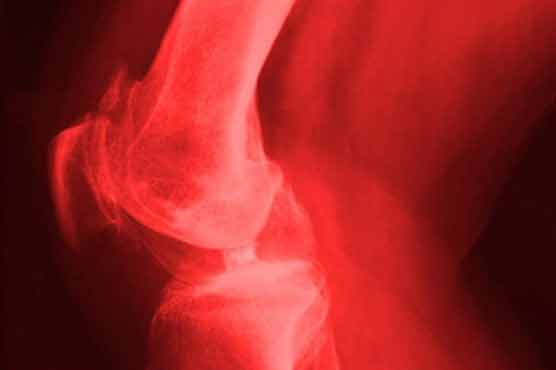

Summary Researchers have developed a potential new approach to treat chronic diseases such as arthritis.

David Fairlie and his colleagues from The University of Queenslands Institute for Molecular Bioscience have developed an experimental treatment that effectively eases symptoms and stops the progression of the disease.Human enzymes called proteases stimulate the secretion of immune cells that, when the correct amount is released, play important roles in digestion, fighting infections and healing wounds, Fairlie was quoted as saying in the journal The Federation of American Societies For Experimental Biology.But in chronic inflammatory diseases such as arthritis, these enzymes continuously stimulate the release of immune cells, which cause inflammation when present at high levels. This leads to ongoing tissue damage, added Fairlie. Inflammation is the bodys response to an injury, infection or illness, according to a Queensland statement.Fairlie and his team have developed experimental compounds that block this stimulation and successfully reduce chronic inflammatory arthritis in experimental models.If the treatment could be transferred to humans, it has the potential to reduce both the health and economic impacts of chronic inflammatory diseases.